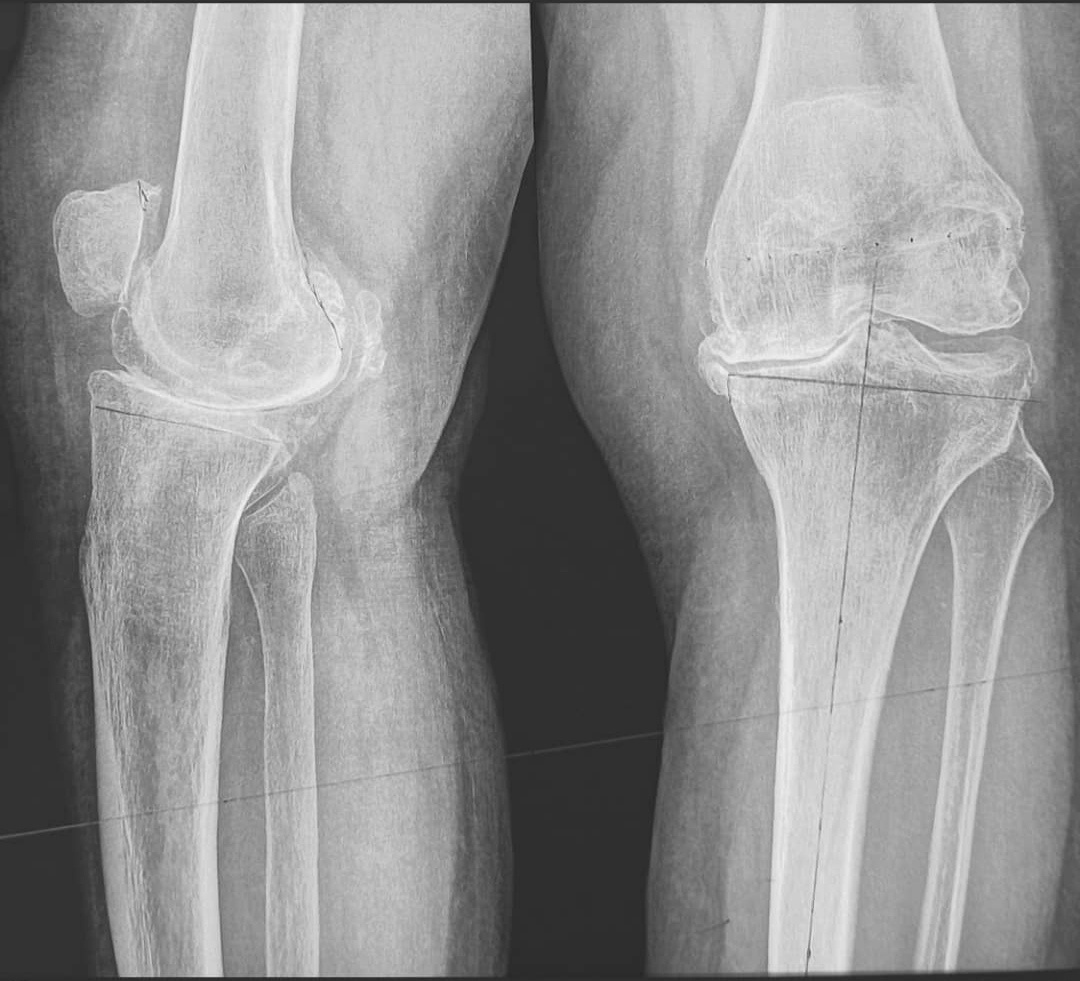

Дегенеративно-дистрофическое заболевание, при котором поражается гиалиновый хрящ, покрывающий мыщелки большеберцовой и бедренной костей. На поздних стадиях гонартроза в процесс вовлекается весь сустав (подлежащая часть кости уплотняется и разрастается). Гонартроз занимает первое место по распространенности среди всех артрозов. Болезнь обычно возникает у пациентов в возрасте старше 40 лет и чаще наблюдается у женщин. В некоторых случаях (после травм, у спортсменов) гонартроз может развиваться в молодом возрасте. Основным проявлением гонартроза являются боли, усиливающиеся при движениях, ограничение движений и синовит (накопление жидкости) в суставе. Лекарственная терапия направлена на оказание противовоспалительного и анальгезирующего эффекта, а также на снижение деструкции хряща. Для решения поставленных задач в современной медицине используются препараты следующих фармакологических групп: -Нестероидные противовоспалительные препараты -препаратоы для внутрисуставных инъекций на основе

Дегенеративно-дистрофическое заболевание, при котором поражается гиалиновый хрящ, покрывающий мыщелки большеберцовой и бедренной костей. На поздних стадиях гонартроза в процесс вовлекается весь сустав (подлежащая часть кости уплотняется и разрастается).

Гонартроз занимает первое место по распространенности среди всех артрозов. Болезнь обычно возникает у пациентов в возрасте старше 40 лет и чаще наблюдается у женщин. В некоторых случаях (после травм, у спортсменов) гонартроз может развиваться в молодом возрасте. Основным проявлением гонартроза являются боли, усиливающиеся при движениях, ограничение движений и синовит (накопление жидкости) в суставе.